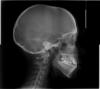

Помогите разобраться с лечением. Девочке 15 лет, клык в десне и неправильный прикус (верхняя челюсть меньше чем нижняя) Врачи сказали не правильное соотношение челюстей. Ходили к двум ортодонтам.

Первый гарантирует исправление прикуса и выравнивание зуба , при этом необходимо удалять 8 зубы на обеих челюстях ( зубы еще не прорезались, нижняя челюсть видны отчетливо , на верхней только зачатки) После консультации с хирургом выяснилось , что верние можно и не удалять), Он предлагает брекеты +несъемную пластину на небо+ винты на нижнюю челюсть.В противном случае после 18 лет операция с удалением 4 зубов.

Второй ортодонт сказала, что пока ничего делать не нужно, так как даже при установке брекетов (при этом нужно удалить 4 зубы) не гарантирован результат по исправлению прикуса и выравниванию клыка.а также еще не известно как это отразиться на эстетике лица . Она сказала, что нужно начать заниматься зубами в 16,5 лет и посмотреть нет ли изменений в росте челюстей. Подскажите как быть и когда все таки зиниматься зубами. У девочки бронхиальная астма легкое течение.